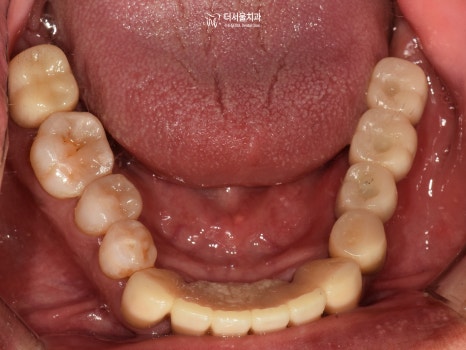

3) 교합면

발치를 하셨기 때문에 텅 비어 있는 곳이 많았습니다.

하악 전치부 쪽이 심각한 것으로 판단이 되네요.

보시다시피 하악 전치부의 문제들이 심각했습니다.

그러나 이쪽에는 또 다른 문제가 있었는데요.

심한 치주 질환으로 공간적으로 뼈가 너무 없었습니다.

즉, 픽스처를 심기에는 어려움이 있다는 뜻이죠.

이후 총 5곳에 implant fixture를 심은 다음

잇몸 형성에 도움을 줄 healing abutment까지 체결을 도왔습니다.

임플란트 치과 의 좌측 과정은

최종 보철을 올려드리며 모두 마무리가 되었습니다.